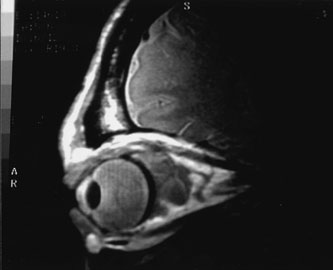

Contrast-enhanced CT of the orbits with direct and coronal cuts is the radiologic study of choice for these patients.45 A well-demarcated, encapsulated oval or rounded mass is revealed, which is typically intraconal in the lateral part of the middle third of the orbit (Fig. 5) but occasionally may extend to the extraconal space.42 Septa within the tumor may be apparent on high-resolution CT. The posterior pole of the globe frequently is indented by the rounded anterior margin of the tumor.42 The optic nerve typically is displaced rather than surrounded by the tumor. Subtle outward bowing of the lateral orbital wall or increase in orbital size may be present, consistent with a long-standing, slowly growing mass lesion.10,42 Enhancement with intravenous contrast occurs and may be homogeneous or inhomogeneous.10,45 Rarely, cavernous hemangiomas may occur as an intraosseous tumor within the orbital or facial bones.42,53–55 Although usually an isolated intraorbital lesion, multiple lesions in one orbit occurred in 8 of 164 (5%) patients of three combined large studies,10,42,45 and bilateral multiple cavernous hemangiomas also have been described.56 In contrast to patients with venous flow malformations in which phleboliths are common, phleboliths are rare in cavernous hemangiomas. Three large studies comprising 164 patients with cavernous hemangioma all reported that no calcification was detected within the tumor.10,42,45If the diagnosis is still unclear or if better definition of details and localization of the lesion is required, then MRI should be performed. Magnetic resonance imaging demonstrates nonspecific characteristics of a lesion isointense to muscle and gray matter on T1-weighted images and hyperintense on T2-weighted images (Fig. 6).57 The lesions show initial central patchy enhancement, which fills up homogeneously within 20 to 60 minutes.58 If ultrasonography is performed, B-scan ultrasonography shows a well-circumscribed mass with a sharply defined anterior acoustic border.23 A-scan ultrasonography shows high reflectivity of the echo signals resulting from the multiple blood-filled vascular channels, regular internal structure with a higher anterior and posterior spike marking the capsule, and moderate sound attenuation (angle of decrease of the echo spike within the lesion).24 Arteriography is not indicated.

Fig. 6. Cavernous hemangioma. Axial magnetic resonance imaging demonstrates a well-defined, homogeneous intraconal mass that is isointense to muscle and gray matter on T1-weighted image (A), and hyperintense on T2-weighted image (B). Note the displacement of the optic nerve and indented posterior globe.